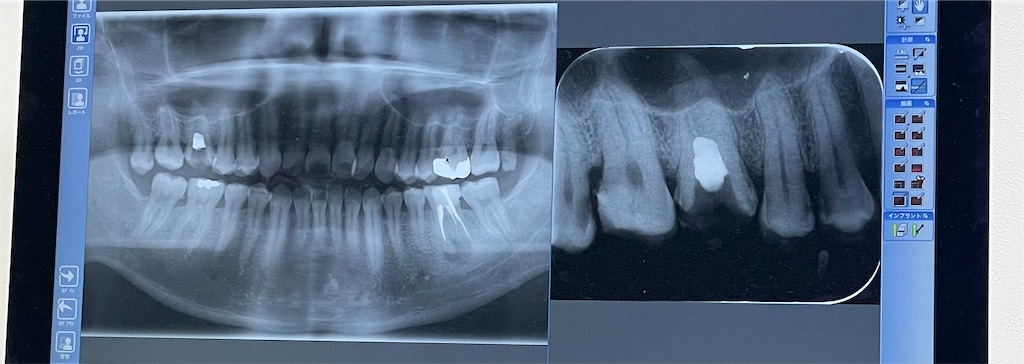

▲白いところは歯じゃないって話

検査の結果は・・・・・

別に何もなってなかったぁぁぁー!!

よかったぁぁぁー( ゚Д゚)ああああーーー!!

神経を抜いてた上の歯(今回の歯)は薬とかは全部なくなってしまってるんだけど、特に問題なさそうなので、薬の打ち込みはせずに詰め物をしてかぶせてOKなんだって!

痛いと思ってたところはその歯の隣の歯の歯茎になんか詰まってたのと、その歯の横部分に虫歯があるとのことでした。悲しい。こんにちは。新しい虫歯さん。

下の奥歯の神経抜いた薬を打ち込んだ下側を見てみ

黒いところ。

歯医者「感染してますね。」

感染しているそうで、治療を早くしてねととです。